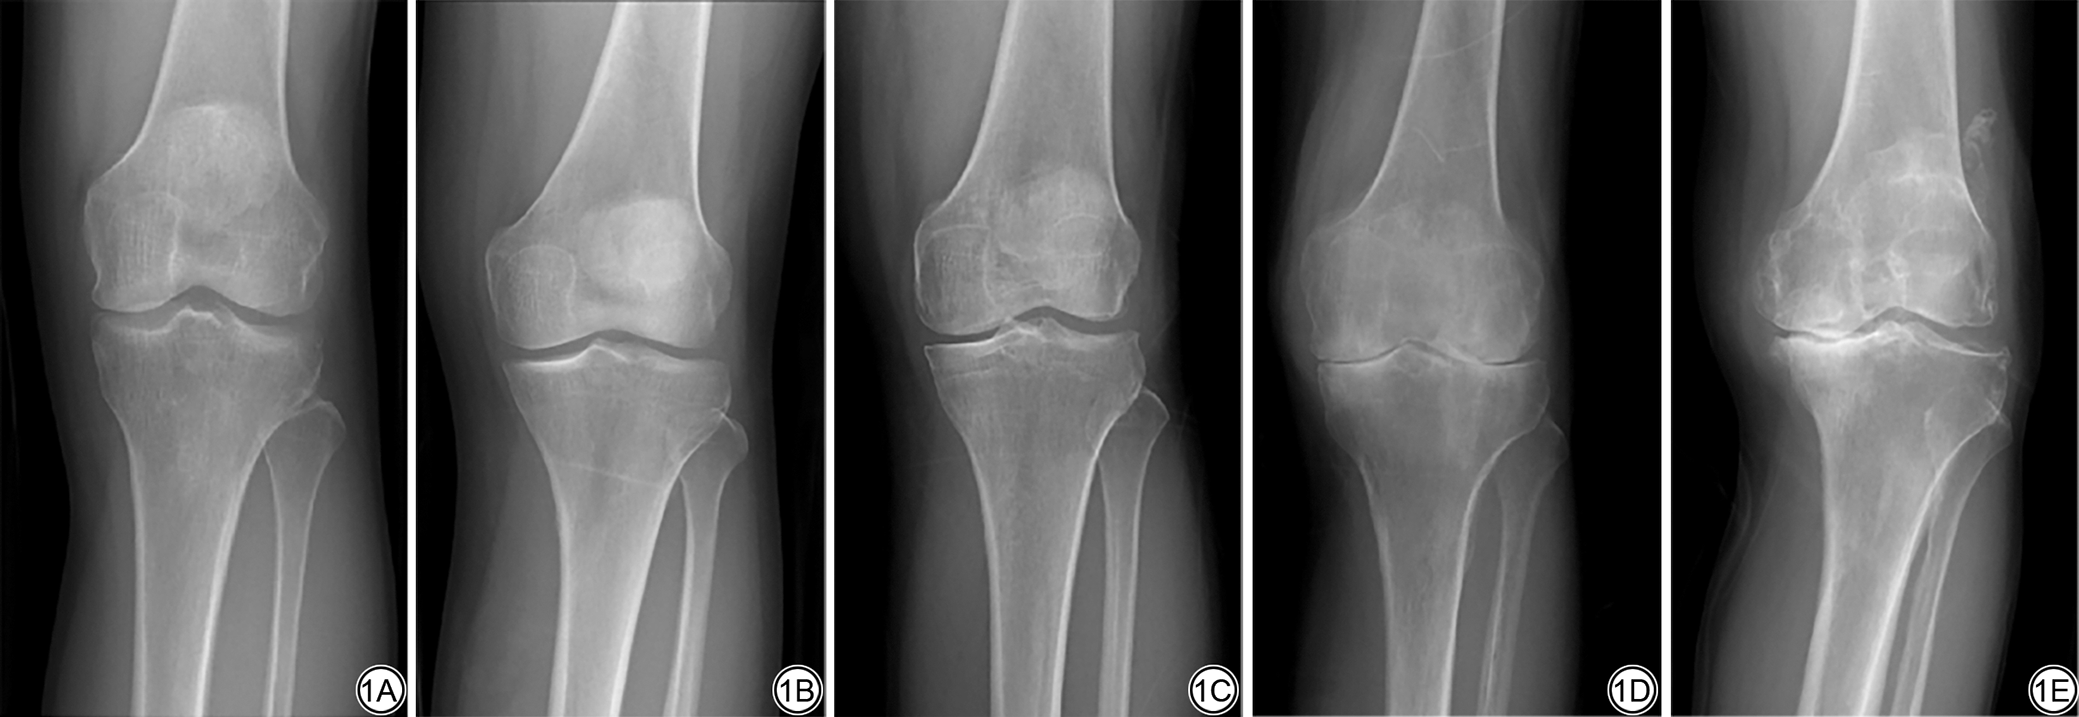

将所有受试者膝关节负重位X线片表现进行KLG[15],共分为4组:KLG 0~1级、KLG 2级、KLG 3级、KLG 4级,如图1所示。

图1  膝关节骨性关节炎Kellgren-Lawrence分级,1A~1E分别为0~4级。

Fig. 1  For the Kellgren-Lawrence grading of knee osteoarthritis, 1A to 1E correspond to grades 0 to 4 respectively.